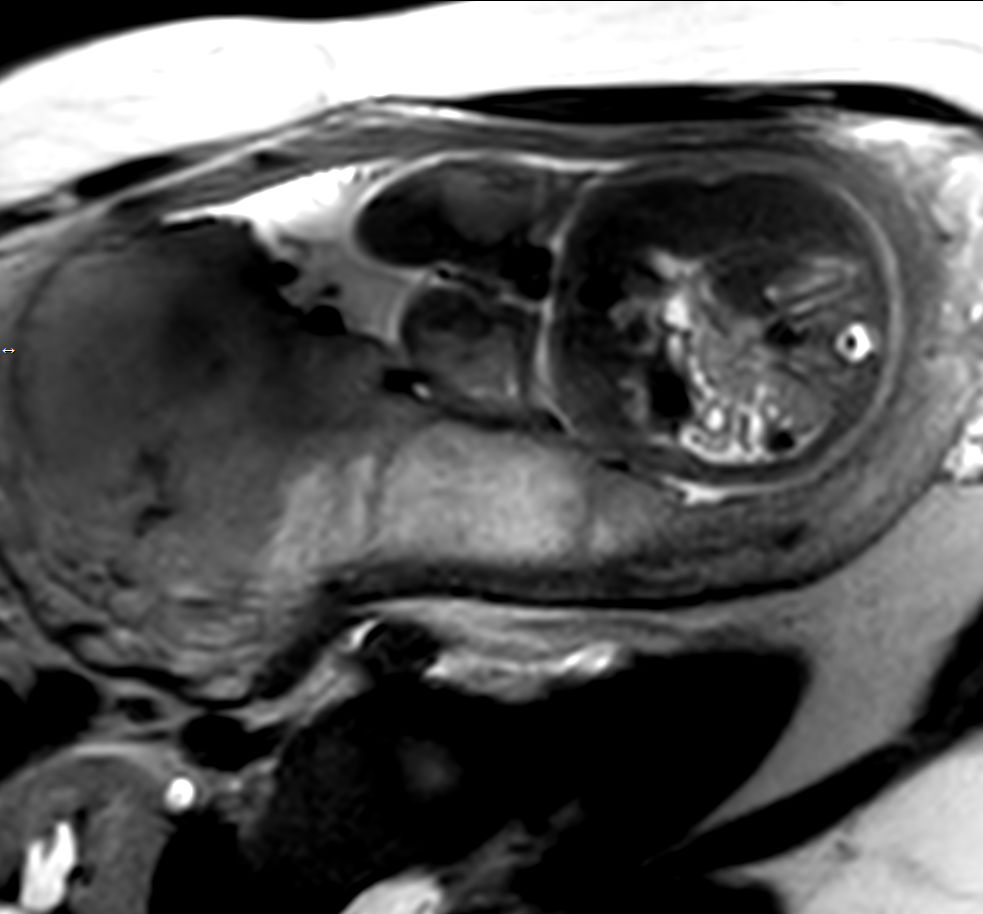

Pregnant patient, referred to MRI for fetal brain and spine imaging.

Sagittal T2w TSE single shotCompressed SENSE